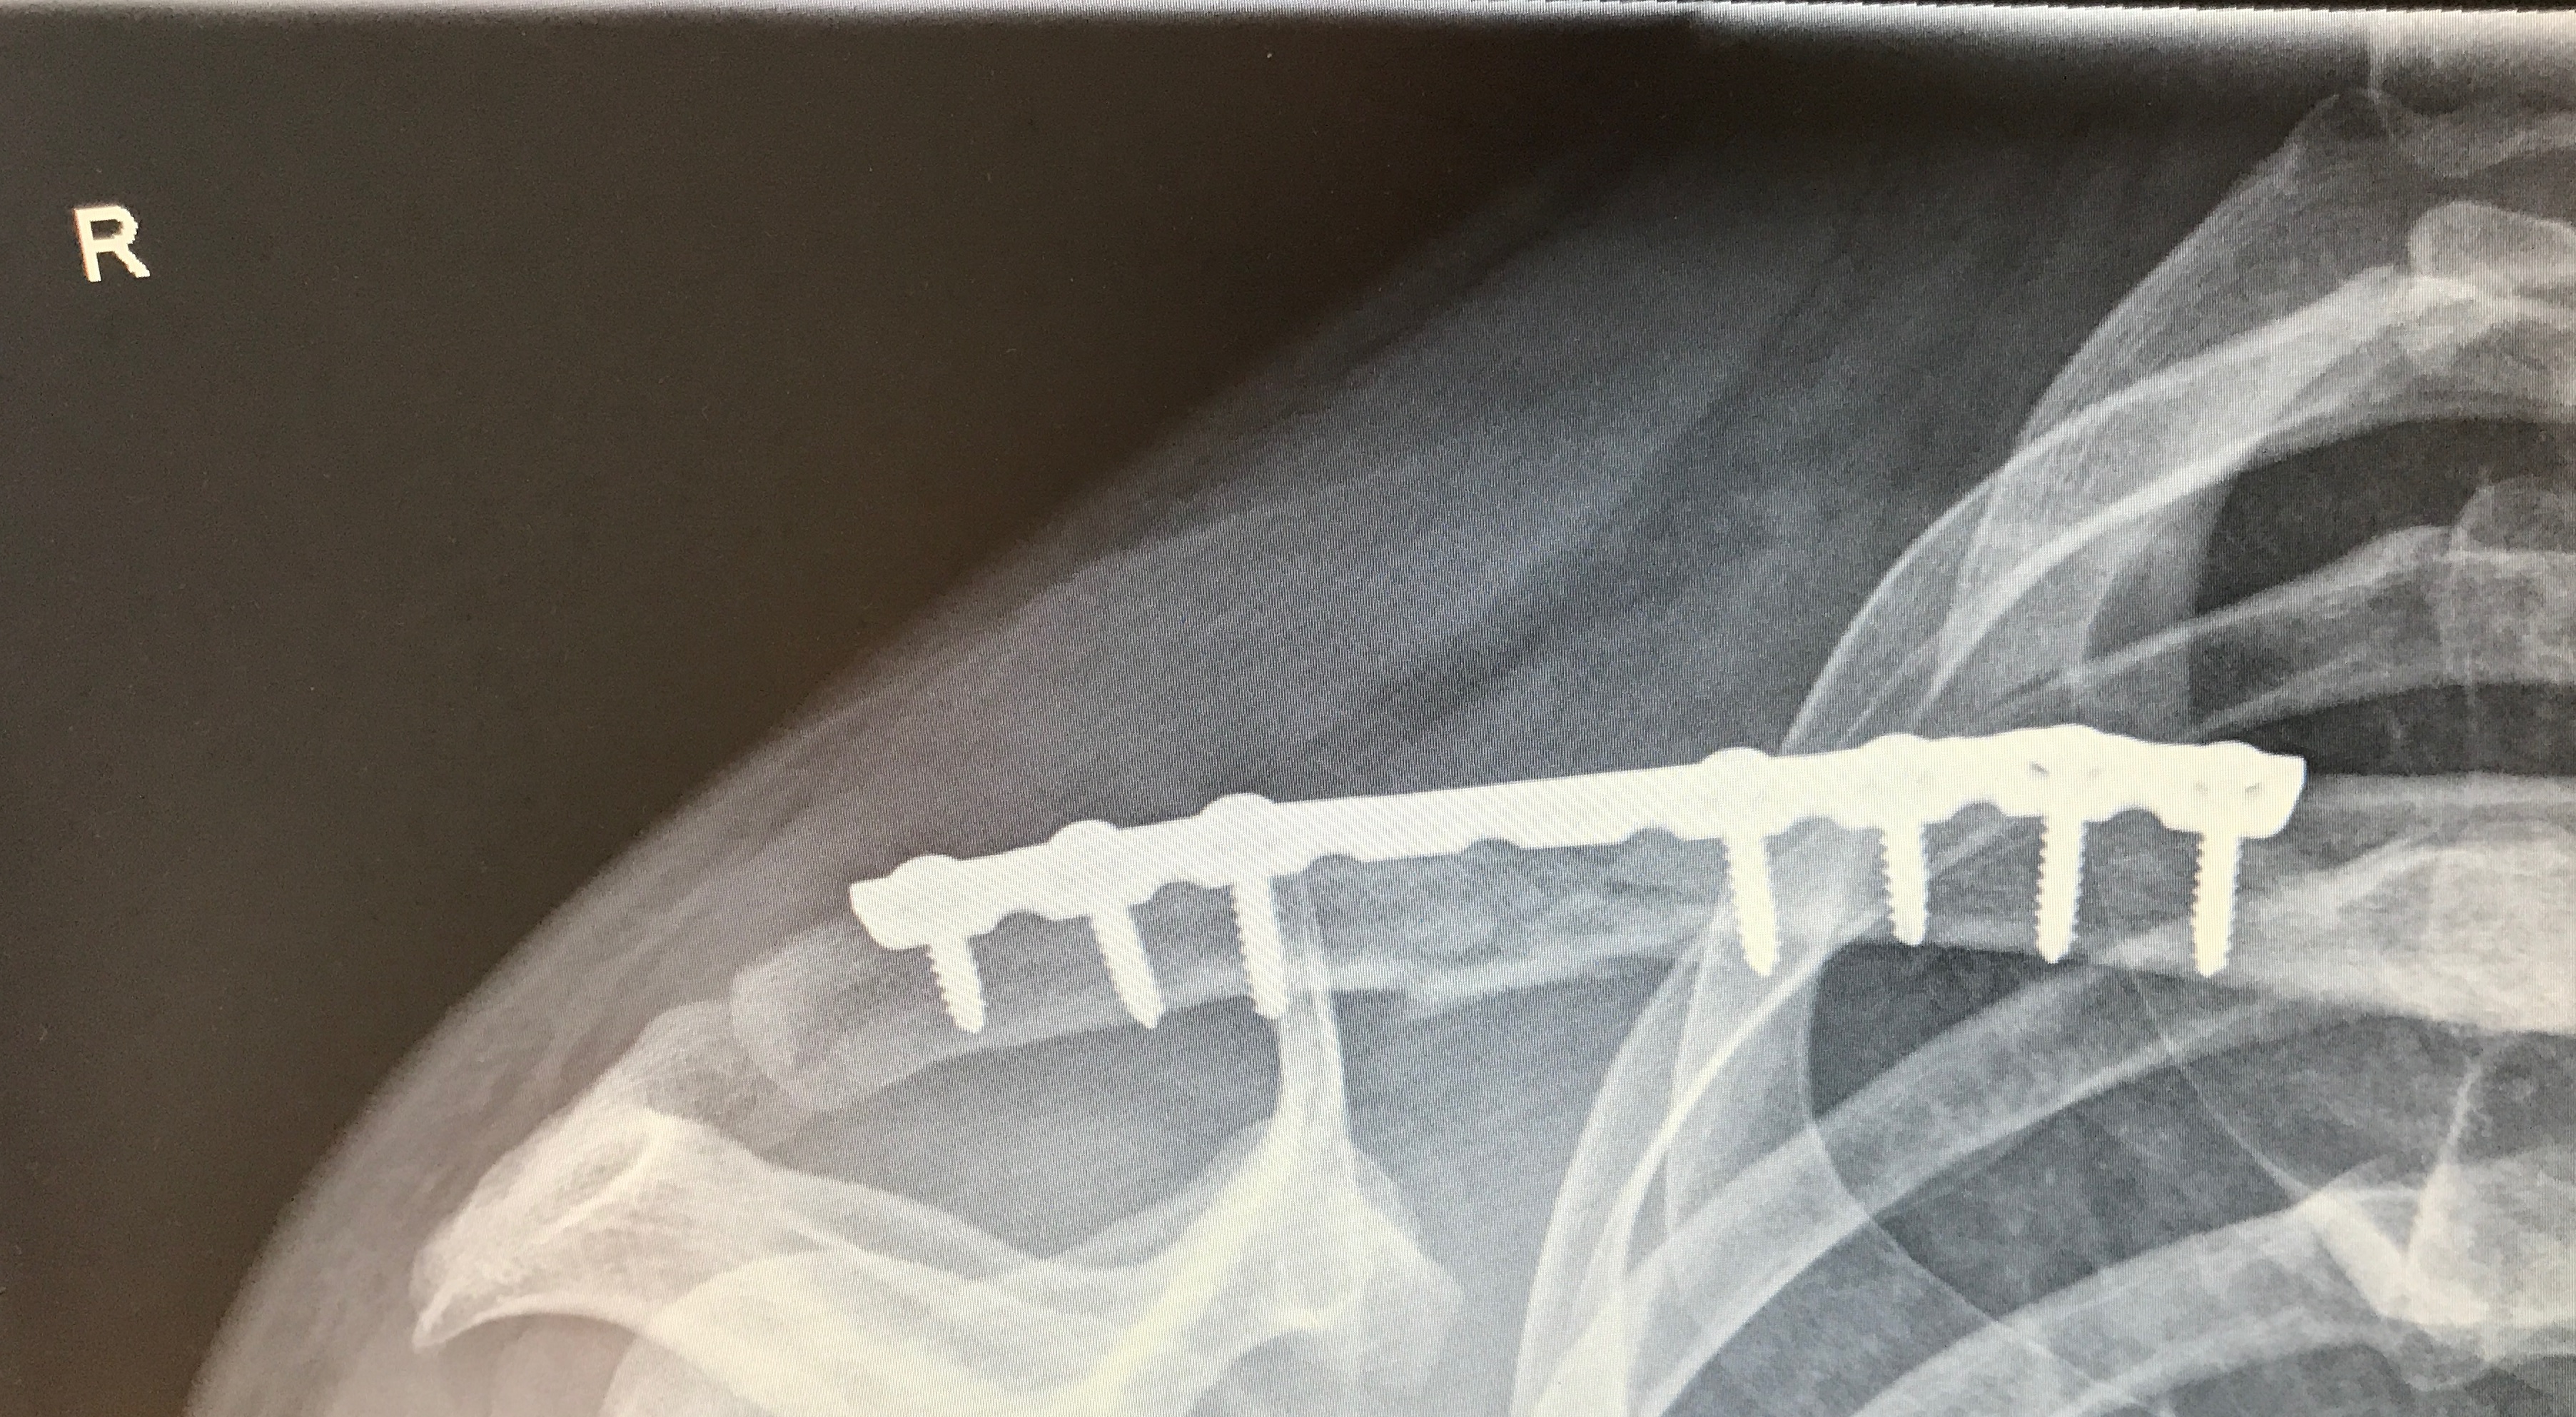

Bei der Titanplatten-Methode war mein Zeitablauf aber so ziemlich gleich. Du hast nur nach der OP halt die größere Wunde (bei mir ca. 13cm lang) und die entsprechende Wundversorgung zu beachten. Das heißt Pflaster immer entsprechend wechseln, nicht nass werden lassen. Das größte Risiko bei der Sache ist nämlich das Infektionsrisiko der Wunde. Auch das mitm nicht über die Schulter den Arm heben usw. war alles gleich.

Saß auch nach einem Wochenende wieder im Büro. Nach 4 Wochen hab ich mich ans Mopped-Schrauben gemacht nach glaub 6 war ich wieder am Joggen + leichtes Gewichte-Training. Nach 8 feuer frei. 10 Wochen nach dem Bruch hatte ich die nächste Veranstaltung und es ging ohne Einschränkungen (außer Kopf :? ).

Aber wenn die Nagel-Methode geht, würde ich sie wegen der kleineren Narbe bevorzugen.

Hast du deine Platte schon rausbekommen? Von den Bildern her könnte es mein Bruch sein, sogar die gleiche Seite :roll:

Ja ist raus. Ende Mai 2017 passiert, Februar 2018 (habs extra in Winter gelegt) dann wieder raus, also ca. 8 Monate.

Raus mit dem Gelump. Haste etwas Titan auf Krankenkasse fürs Mopped. Und mit Platte stürzen ist nicht so geil, bricht dann ja an den Plattenenden, also nicht Mitte sondern eher zum Gelenk hin.

Die OP zum Rausmachen dauerte genau 20 min. Mittags rein, Abends raus (viel Warterei dabei, lag aber an dem Krankenhaus). Hast halt wieder die Wunde zu versorgen 2-3 Wochen. Dann noch 2-3 Wochen etwas aufpassen, der Knochen ist ja quasi perforiert durch die Schraubenlöcher und dann sind die wieder verheilt und alles ist tutti.